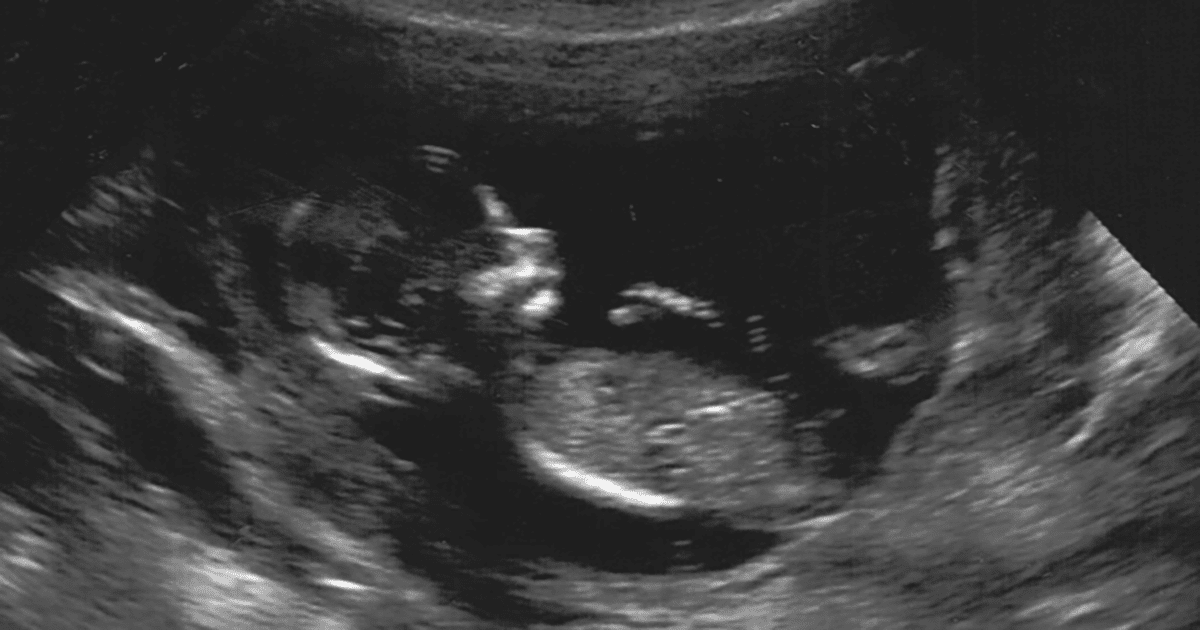

ToggleTijdens je zwangerschap worden er standaard een aantal echo’s gemaakt. Dit is een onderzoek waarbij er met geluidsgolven een beeld wordt gemaakt van uw baby. Dit onderzoek doet geen pijn.

Vanaf 5 weken en 3 dagen zwangerschap klopt het hartje van de baby bij een intacte zwangerschap. Om zeker te weten dat het hartje zichtbaar is op de echo, wordt de eerste echo gedaan met 7 weken zwangerschap. Ook wordt er gekeken of de baby in de baarmoeder groeit. Deze echo wordt niet standaard gedaan, maar alleen op medische indicatie. Echter, Verloskundigenpraktijk PuurBegin biedt deze echo gratis aan.

In principe worden echo gedaan aan de buitenkant van je buik. Hiervoor moet de buik bloot zijn, maar je hoeft je BH en broek niet uit te doen. Er wordt wat gel op de buik gedaan om met het aparaat te kunnen kijken naar de baarmoeder en baby. Omdat de baarmoeder met 8 weken nog heel klein is en achter je schaambot zit, kunnen de geluidsgolven van de ech hier soms niet doorheen. Het lukt dan niet om het hartje van de baby te zien met een echo aan de buitenkant van de buik. Het is belangrijk om het hartje van de baby goed in beeld te krijgen, om te vertellen of de zwangerschap nog intact is. Daarom wordt deze vroege echo altijd via de vagina inwendig gedaan. Een inwendige echo doet geen pijn, maar kan wel een gek gevoel zijn. Als je in het verleden een vervelende ervaring hebt gehad met een inwendig onderzoek of op seksueel gebied, kan een inwendige echo minder prettig zijn. Als het niet gaat, kun je de hand van degene pakken die de echo maakt. Hiermee weten we dat er even pauze moet worden genomen en kunnen we rekening met je houden.